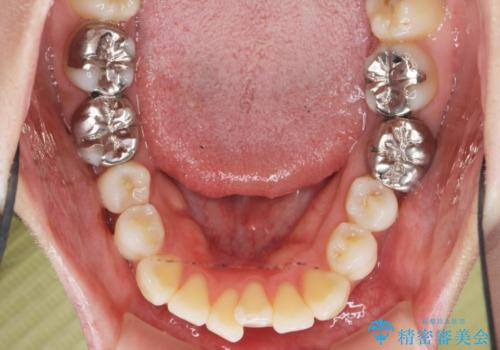

捻れた奥歯 突き出た前歯を治したい

- 出っ歯に見える前歯、捻れてしまった小臼歯の改善を求めて来院されました。

マウスピースでは改善の難しい小臼歯のねじれをまず部分ワイヤー矯正で改善し、その後マウスピース矯正で前歯の突出感を改善します。

時間はかかりましたが、捻れ、かみ合わせ、前歯の角度の改善が達成され満足いただくことができました。